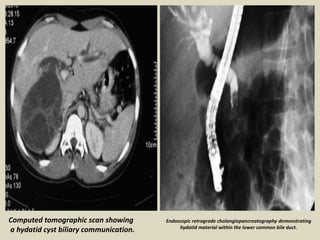

Hydatid cyst ruptured into the biliary tract A 45 years old female, with a history of cholecystectomy 10

years ago, presented with abdominal pain. (a) Abdominal US revealed a multivesicular hydatid cyst of

the liver dome (Gharbi type III). (b) Communication of the hydatid cyst with the right bile duct, and

presence of a hydatid material in the bile duct. (c,d) CT shows the dilated bile ducts, the communication

of the cyst with the right bile duct, and the presence of hydatid material into the biliary tract. (e)

Intraoperative cholangiography showed the presence of hydatid vesicles in the lower bile duct.

Endoscopic retrograde cholangiopancreatography demonstrating

hydatid material within the lower common bile duct.

Computed tomographic scan showing

a hydatid cyst biliary communication.